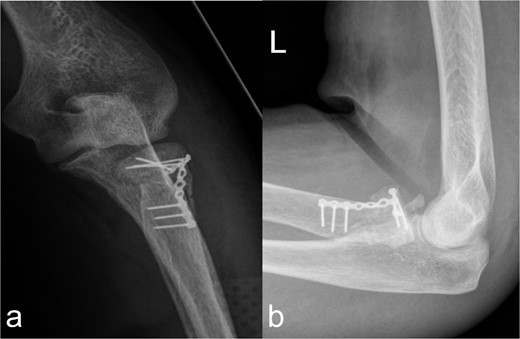

Treatment patterns of supra-intracondylar multifragment fracture (33C3.2). (a) The anterior-posterior and (b) lateral radiographs show a correct position of the osteosynthesis material with an nearly anatomical fracture position.

Using a 3-hole LCP plate (PHILOS-Synthes®) for the humerus (Fig. 4a and b) and a locking T-plate with two additional screws (Synthes®) for the caput and collum radii (Fig. 5a and b), adequate reduction and mostly axial alignment of the fractures were achieved.

Treatment patterns of fractures of the caput and collum radii (2R1C3 and Mason stages II and III). (a, b) X-ray in two planes shows extensive coverage of the fracture fragments of the caput radii when the collum radii is straightened by the osteosynthesis material.

In the fractures described, the osteopenic bone texture with rarefied spongiosa, thinning of the cortical bone and dislocated fragments present an intraoperative challenge in achieving a good reduction in an axially correct position and hardware fixation. In order to achieve the best possible primary stability in the acute situation and to minimize the occurrence of secondary fractures, locking plates, screws with different threads, intramedullary nails, wire cerclage, total endoprostheses, and additional PMMA cement augmentation are used [9–14]. In our patient, this was achieved by means of plate osteosynthesis and additional screws. In the complex multifragment fracture of the distal os femoris, lateral and medial plate insertion was performed to achieve sufficient stability (Fig. 2a and b). This minimizes the development of pseudarthrosis, while lateral and medial plate osteosynthesis does not have a negative influence on vascularity [15, 16]. However, even in nonorgan transplanted patients after optimal osteosynthesis of a distal femur fracture, a second surgery is necessary in every eighth patient [17]. In the case of multiple localizations with more complex fracture courses, several operations and follow-up procedures may be necessary. This necessitates extensive postoperative care, especially in organ transplant patients. Chiou et al. [18] report a 62.5 % mortality rate over the course of 1076 days in lung transplant patients after treatment of a fracture of the lower extremity.